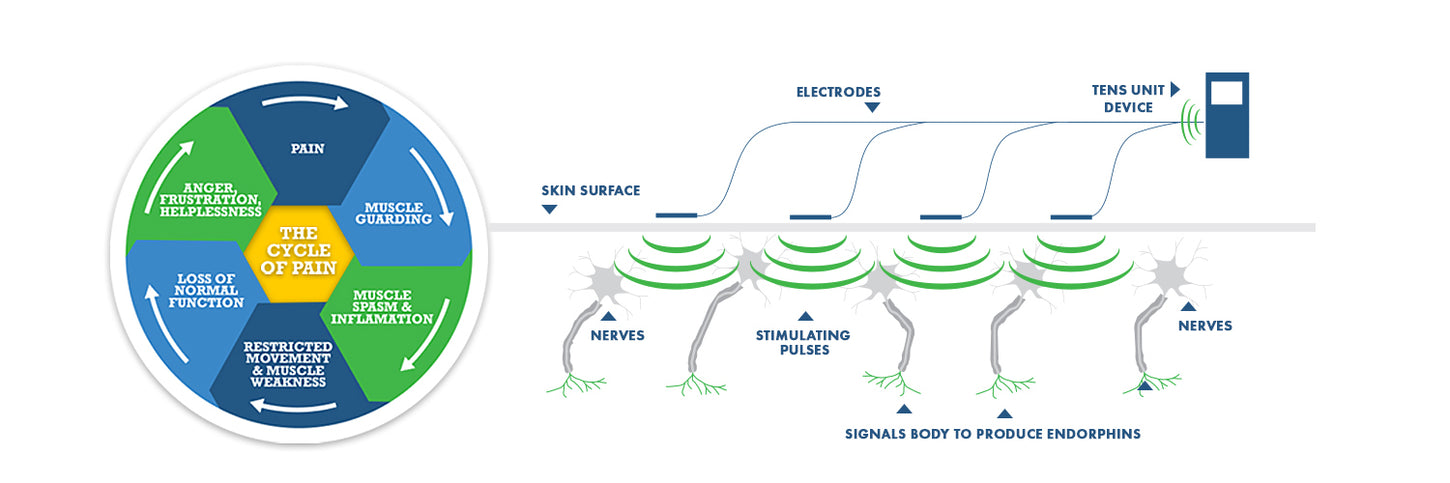

TENS stands for (Transcutaneous Electrical Nerve Stimulation). TENS therapy units are predominately used for nerve related pain conditions (acute and chronic conditions). TENS machines work by sending stimulating pulses across the surface of the skin and along the nerve strands.

The stimulating pulses help prevent pain signals from reaching the brain. TENS devices also help stimulate your body to produce higher levels of its own natural painkillers, called "Endorphins".